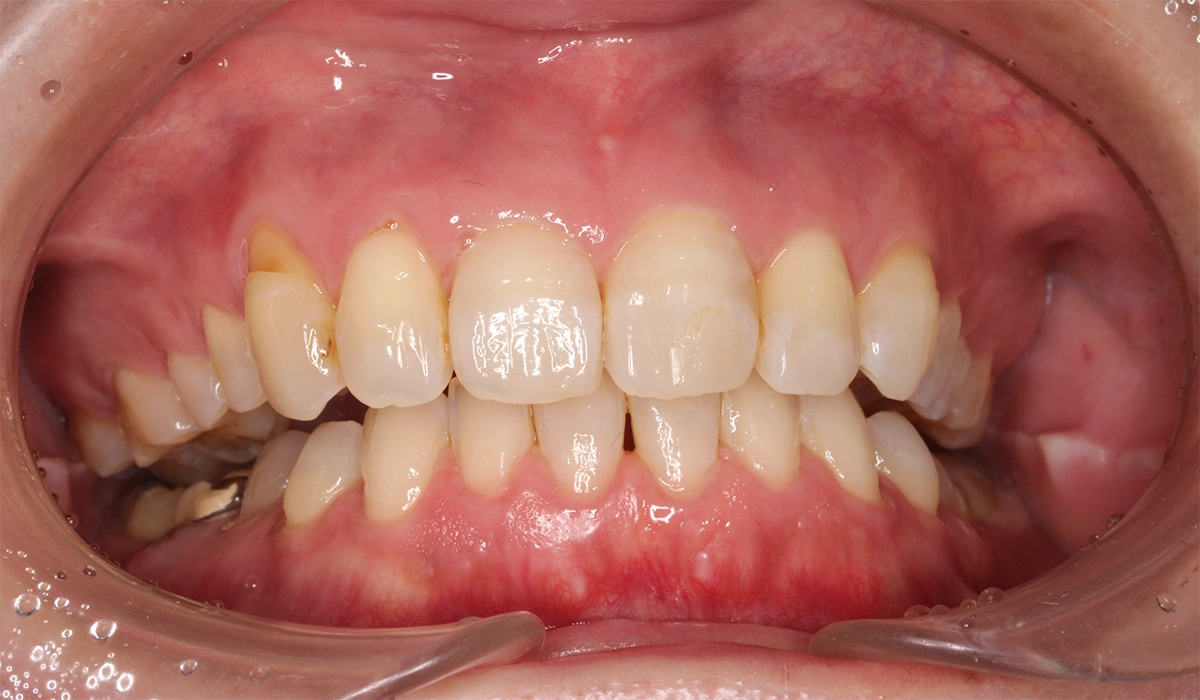

術後:正面